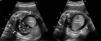

Fetal echocardiogram at 35 weeks of gestation (4-chamber view): single cardiac mass adjacent to the left ventricle (57 mm×43 mm), with well-defined contours and homogeneous echogenicity, mild left ventricular compression and moderate pericardial effusion (arrows). LA: left atrium; LV: left ventricle; RA: right atrium; RV: right ventricle.

The authors report the case of a 29-year-old woman with an uneventful pregnancy until 35 weeks of gestational age, when a single fetal giant cardiac mass and moderate pericardial effusion were detected on a routine fetal obstetric scan. The mass measured 57 mm×43 mm and was adjacent to the anterior and lateral walls of the left ventricle, causing mild compression, with no signs of inflow or outflow tract obstruction (Figure 1, Videos 1-3). Global cardiac function was preserved and no signs of hemodynamic compromise were documented. All findings were considered consistent with a single cardiac rhabdomyoma.